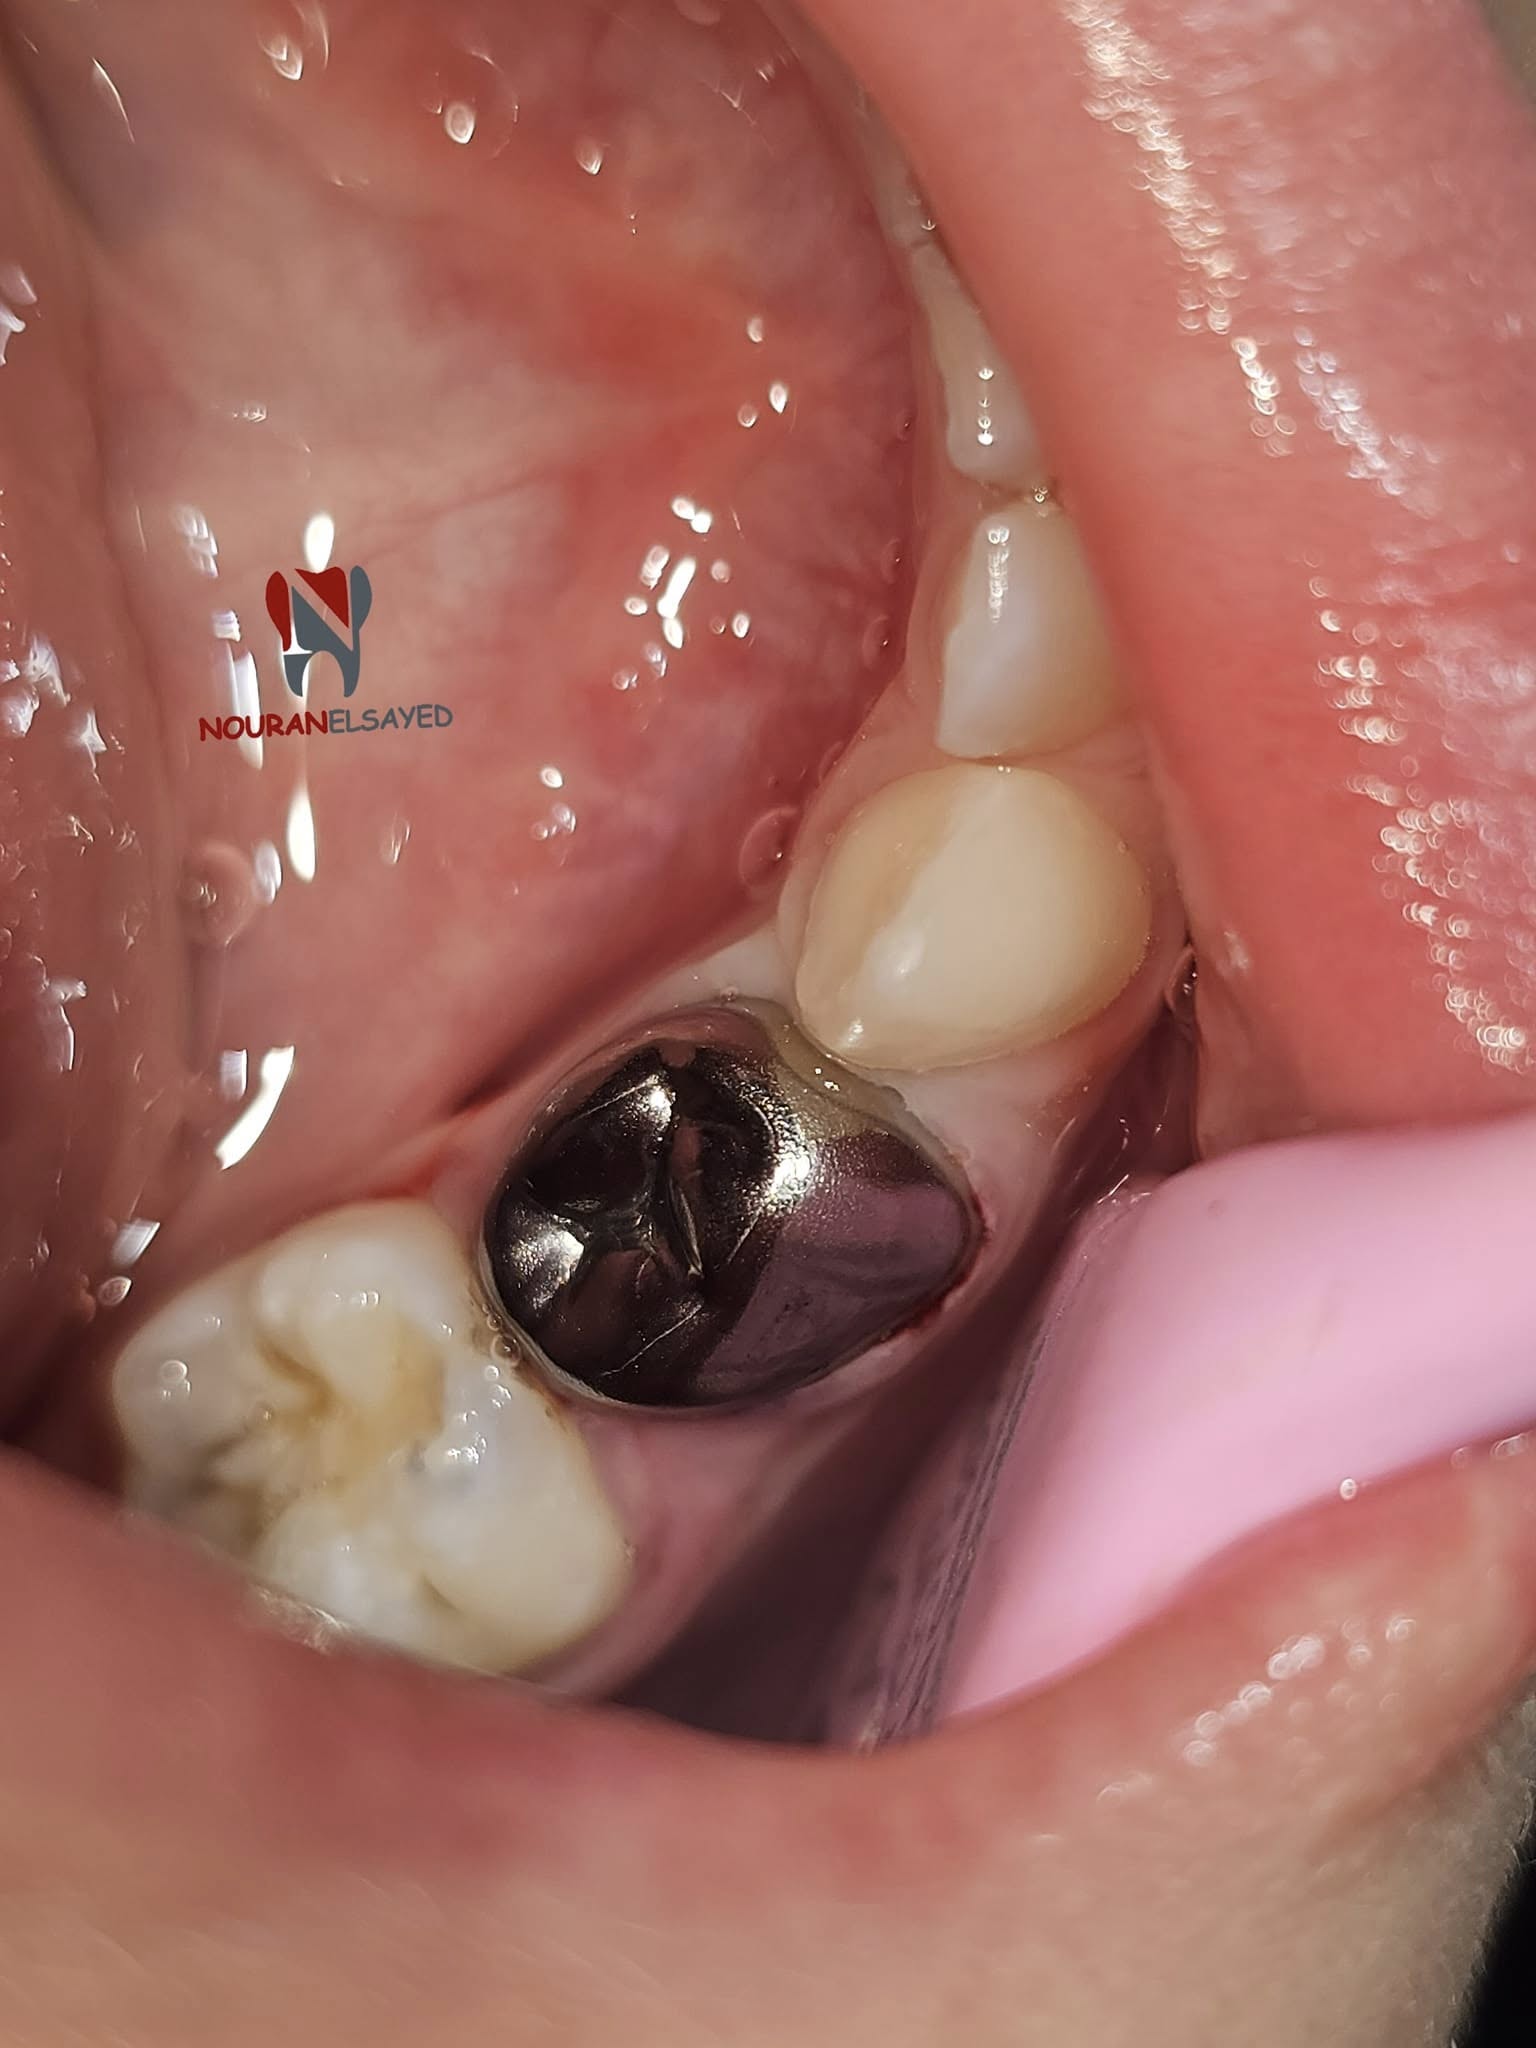

الحفاظ على صحة العصب و تغطيته بالطربوش المعدن

الحفاظ على صحة الاسنان و العصب